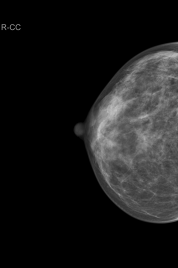

Mamografía

En qué consiste una mamografía

La mamografía es un tipo específico de imágenes que utiliza un sistema de dosis baja de rayos X para examinar las mamas. Un examen de mamografía, llamado mamograma, se utiliza para asistir en la detección temprana y el diagnóstico de las enfermedades mamarias en las mujeres.

Dos recientes avances a la mamografía tradicional incluyen la mamografía digital y la detección asistida por computadora.

La Mamografía digital, también llamada mamografía digital de campo completo (MDCC), es un sistema de mamografía en el que la película de rayos X es reemplazada por detectores en estado sólido que transforman los rayos X en señales eléctricas. Estos detectores son similares a los que tienen las cámaras digitales. Las señales eléctricas se utilizan para producir imágenes de las mamas que pueden verse en una pantalla de computadora o ser impresas en una película especial similar a los mamogramas convencionales. Desde el punto de vista del paciente, tener una mamografía digital es esencialmente lo mismo que tener un mamograma convencional de pantalla-película.

Los sistemas de detección asistida por computadora (AC) utilizan una imagen mamográfica digitalizada que puede obtenerse ya sea de un mamograma convencional de película o un mamograma adquirido digitalmente. El software de la computadora entonces busca áreas anormales de densidad, masa o calcificación que puedan indicar la presencia de cáncer. El sistema de detección asistida por computadora resalta estas áreas en las imágenes, alertando al radiólogo de la necesidad de análisis adicionales.

Los mamogramas son utilizados como una herramienta de exploración para detectar de manera temprana el cáncer de mamas en las mujeres que no tienen síntomas (mamografía de exploración) y para detectar y diagnosticar enfermedades mamarias en mujeres que tienen síntomas tales como bultos, dolor o secreción del pezón (mamografía diagnóstica).

Mamografía de exploración

La mamografía juega un papel central en la detección temprana del cáncer de mamas ya que puede mostrar los cambios en las mamas hasta dos años antes de que el médico o paciente los adviertan. realizarse una mamografía de exploración cada año en las mujeres, comenzando a partir de los 40 años. La investigación ha demostrado que los mamogramas anuales llevan a la detección temprana del cáncer de mamas, etapa en la que tienen mayores posibilidades de curación y se encuentran disponibles terapias de conservación de mamas.

Mamografía de diagnóstico

La mamografía de diagnóstico se utiliza para evaluar a una paciente con resultados clínicos anormales—tales como nódulos o bultos en las mamas—descubiertos por la mujer o su médico. La mamografía de diagnóstico también puede realizarse luego de una mamografía de exploración anormal con el fin de evaluar el área conflictiva en el examen de exploración.